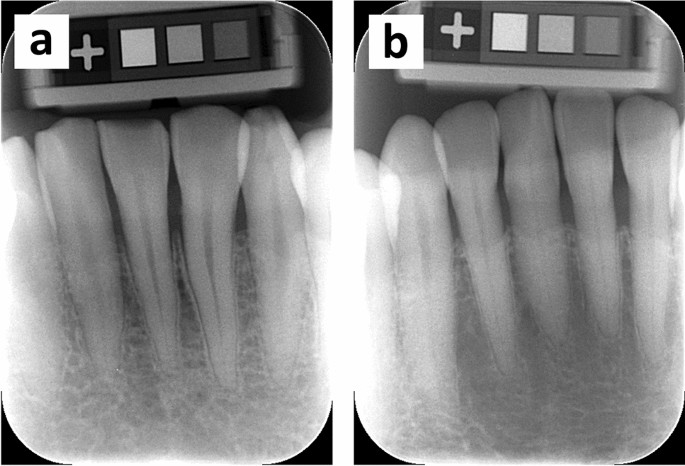

Two representative examples of intraoral radiography demonstrating the highest and lowest al-BMD values are shown in Fig. 2 (a: 1259.26 mg/cm2, male 28 years; b: 495.24 mg/cm2, female 78 years). As seen in Fig. 2a, well-mineralized trabeculae, and small intertrabecular spaces were predominantly observed within the periapical region of the incisors. Conversely, the trabeculation pattern in Fig. 2b was sparse and irregular.

Two representative radiographic images demonstrating the highest (a: 1259.26 mg/cm2, male, 28 years) and lowest (b: 495.24 mg/cm2, female, 78 years) al-BMD values in the analysis. Dense trabeculation (a) and sparse trabeculation pattern (b) are predominant. Marginal bone loss is commonly less than two-thirds of the root length.